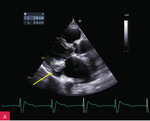

W badaniu echokardiograficznym przezklatkowym (TTE – transthoracic echocardiography) uwidoczniono guzowatą zmianę o wymiarach 37 × 28 × 25 mm u podstawy tylnego płatka zastawki mitralnej i w obrębie ściany dolno-bocznej lewej komory, o nierównej powierzchni od strony komory, nieznacznej ruchomości zgodnej z ruchem serca i niejednorodnej echostrukturze ze zwapnieniami (ryc. 2-5). Powodowała ona niewielkie ograniczenie ruchomości płatków zastawki mitralnej z utrudnieniem napełniania komory i parametrami małej stenozy (ryc. 6). Stwierdzono ponadto małą niedomykalność mitralną (ryc. 6), dużą niedomykalność trójdzielną, znacznie powiększone obydwa przedsionki oraz w niewielkim stopniu prawą komorę w zakresie drogi odpływu, a także niewielki przerost ścian lewej komory. W badaniu nie stwierdzono wyraźnych odcinkowych zaburzeń kurczliwości lewej komory. Globalna funkcja skurczowa lewej i prawej komory była zachowana w dolnych granicach normy: frakcja wyrzutowa lewej komory (LVEF – left ventricular ejection fraction) 50%, skurczowe przemieszczenie płaszczyzny pierścienia trójdzielnego (TAPSE – tricuspid annular plane systolic excursion) 18 mm. Stwierdzono cechy dysfunkcji rozkurczowej lewej komory z cechami wysokiego ciśnienia napełniania. Zarejestrowano również małą ilość płynu w osierdziu (do 6 mm za ścianą boczną lewej komory).

Rycina 9A-C. Kontrolne badanie echokardiograficzne przezklatkowe (TTE) po 5 miesiącach od rozpoznania uwidoczniło porównywalne wymiary zmiany guzowatej jak w badaniu wyjściowym (A), brak progresji zwężenia zastawki mitralnej (B), charakterystyczny obraz uwapnionej otoczki z bezechowym rdzeniem wewnętrznym (C)

Biorąc pod uwagę stabilny obraz kliniczny po zastosowaniu leczenia farmakologicznego i zabezpieczeniu chorej stałą stymulacją serca oraz brak istotnej wady zastawki mitralnej, pacjentkę zakwalifikowano do leczenia zachowawczego i obserwacji z regularną oceną echokardiograficzną (ryc. 9).